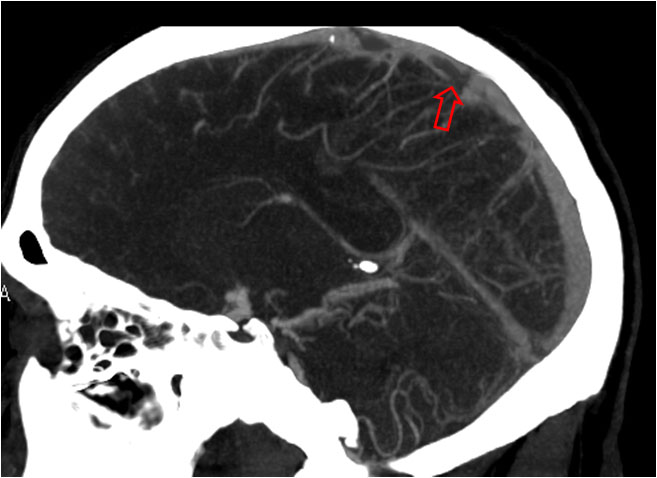

En el mismo paciente, un corte más apical en la TC craneal sin contraste (a la izquierda) muestra la hiperdensidad del seno longitudinal (flecha) por trombosis. La imagen de la derecha es una reconstrucción sagital de línea media del angioTC. La flecha señala un defecto de repleción por trombo en el interior del seno. Existe otro defecto más anterior. Se trataba, pues, de una trombosis parcial. Por esa razón no se ve el signo del triángulo denso en el primer corte.